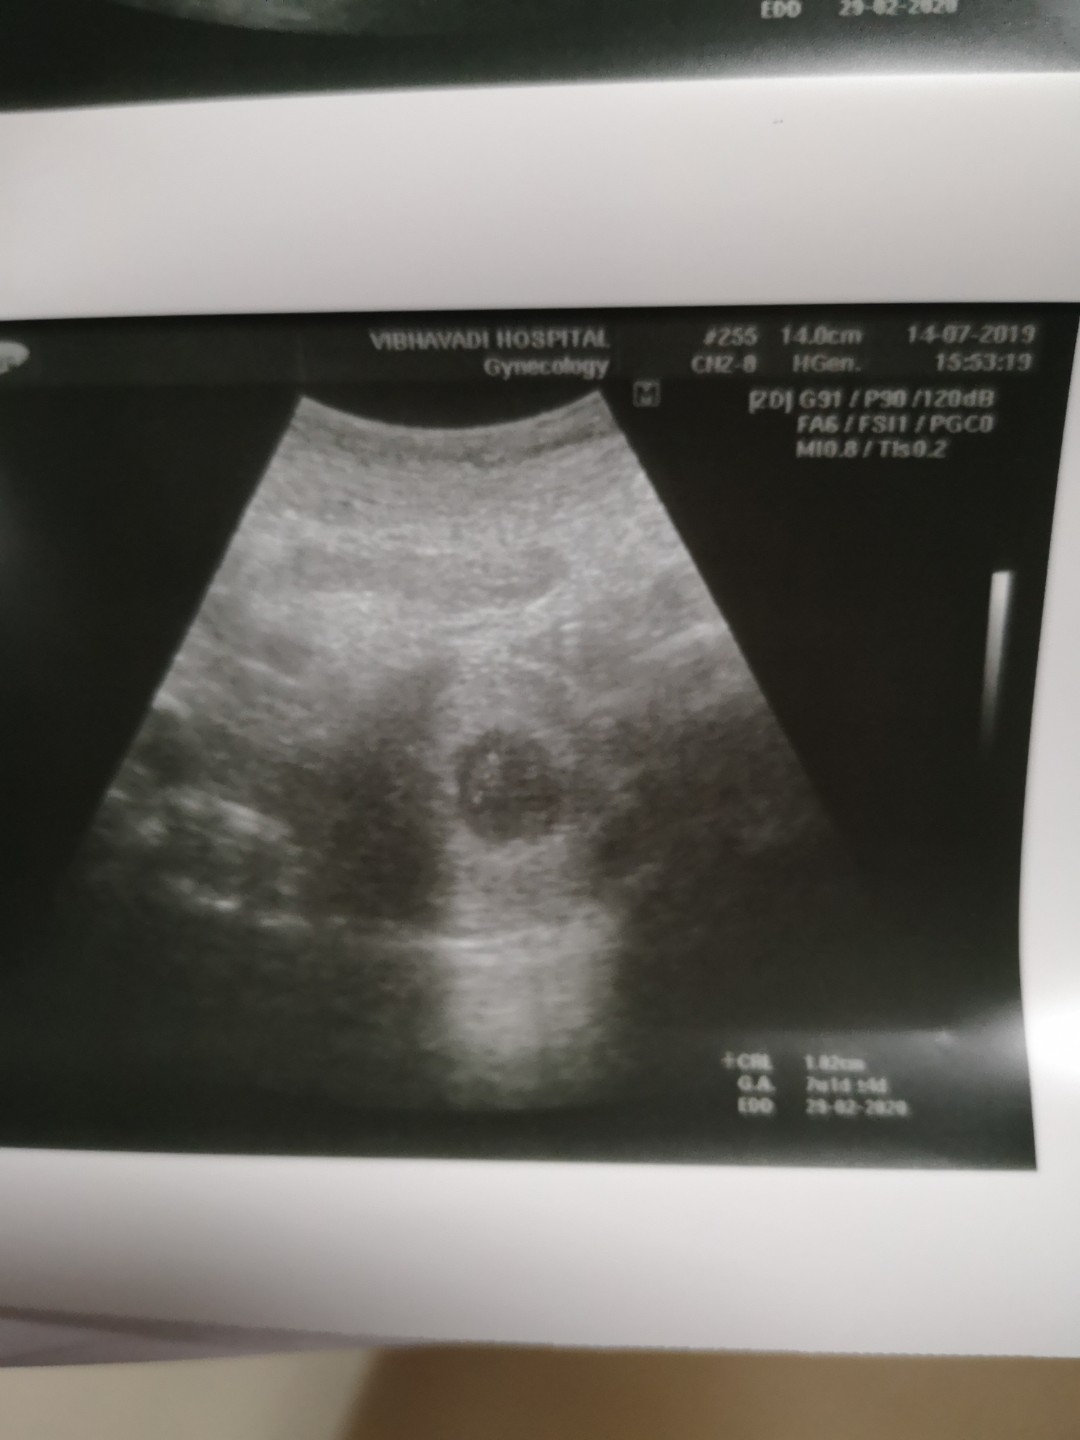

7วีค ผ่านหน้าท้อง เจอน้องแล้วค่ะ แต่ตัวเล็กมาก U/Sยี่ห้อซัมซุงไม่ชัดเลย

บ้านนี้7wเห็นประมาณนี้คะ ตอนนี้จะ14wแล้วคะ สู้ๆนะคะแม่ เดี๋ยวก็เจอน้องคะ